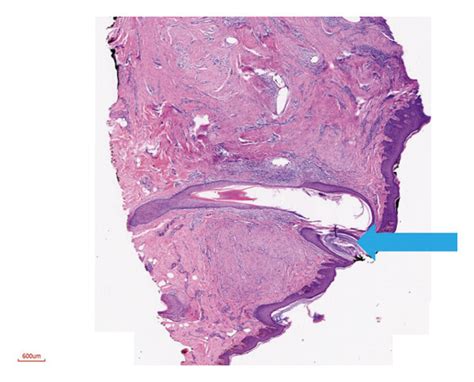

These cysts can range in size from small to quite large, and their presence can lead to a variety of symptoms. Pain, especially during menstruation, is a common complaint. The pain might be cyclical, worsening with each period. Irregular bleeding or spotting can also occur. If the cyst is large enough, it might press on nearby organs, leading to issues like painful urination or bowel movements. In some cases, a pseudohorn cyst can be asymptomatic and only discovered incidentally during a pelvic exam or imaging for another reason. It’s important for women experiencing persistent pelvic pain, irregular bleeding, or other concerning symptoms to see a gynecologist. Early diagnosis is key, as untreated, these cysts can potentially lead to complications such as infection or even affect fertility in some individuals. The diagnostic process usually involves a thorough medical history, a physical examination, and imaging techniques like ultrasound, MRI, or CT scans to visualize the cyst and determine its exact nature and location. The term “pseudohorn” specifically relates to the appearance on imaging, where it might resemble a horn-like structure due to its shape and the surrounding tissue. This visual characteristic is what gives it its distinctive name in medical literature. It’s a reminder that our bodies can sometimes develop in ways that require careful medical attention and understanding.